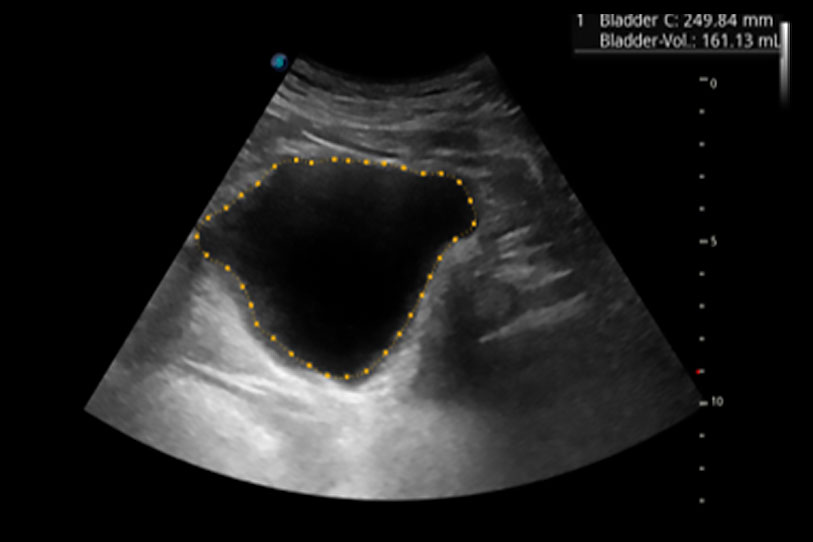

一鍵自動識別膀胱壁及自動測量膀胱容積,不受膀胱形狀和大小的限制,幫助醫(yī)生快速精準獲得測量的數(shù)據(jù)。